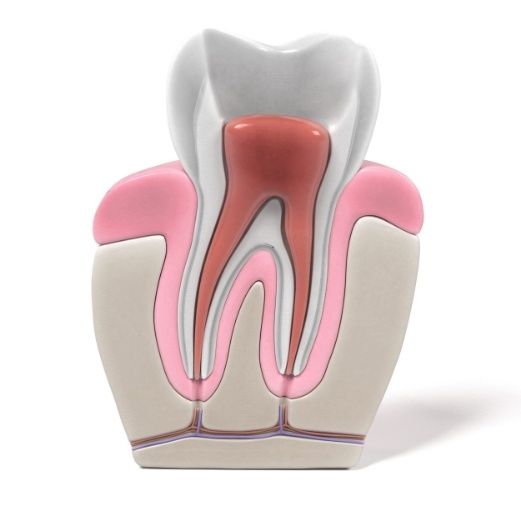

What Is a Root Canal?

Root canal treatment is the process of devitalizing the tooth by removing the dental pulp affected by inflammation/infection, causing pain. The procedure is necessary to alleviate discomfort, cure the infection, and preserve the tooth’s function for years to come.